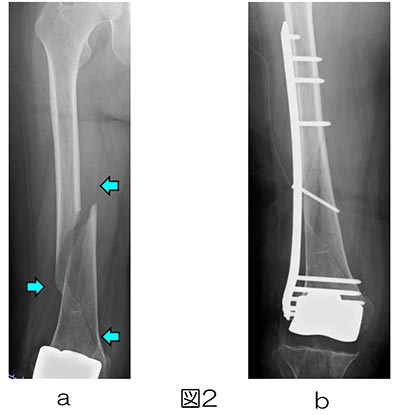

メルカリで裁断済み商品を購入しております。裁断済み商品であること確認お願いします。書き込み等はありませんが濡らした跡があります。「インプラント周囲骨折を極める」馬場智規定価: ¥ 15000